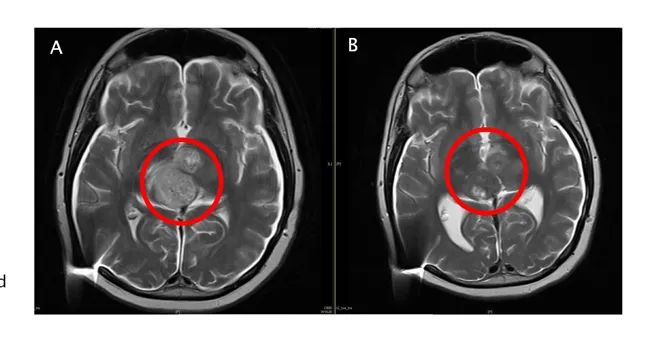

图A:入组前核磁影像,红圈内显示有大量的弥漫性病灶。

图B:ACT001单药治疗后影像,肿瘤细胞密度大幅降低。